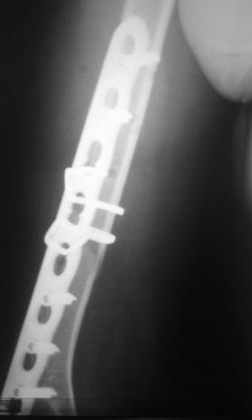

Да, как раз блокированная пластина и стоит, не синтезовская метадиафизарная, Рыбинская, но на порядок дешевле, а профилактика всех осложнений - в данном конкретном случае, начало ранней на вторые сутки - после удаления дренажа разработки движений в смежных суставах. Если же идти с ревизией т.е. всё равно, открыто как вариант небольших разрезов при поперечном переломе можно и комбинированный мос (см.на вкладыше), хотя думаю для такого способа перелом всётаки низковат.

Всё правильно, просто я несколько разрозненно пытался сказать на частных примерах, то , что Вы систематизировали. Совершенно верно данный перелом можно и так и эдак, наиболее оптимально антеградное штифтование, хотя я бы предпочёл пластину LCP(просто - ну лучше у меня это получается и всё, а больному не вредит тот же функциональный способ). А низковато для неблокированного штифтования с конструкциями с термомеханической памятью, то, что представленно на втором снимке.